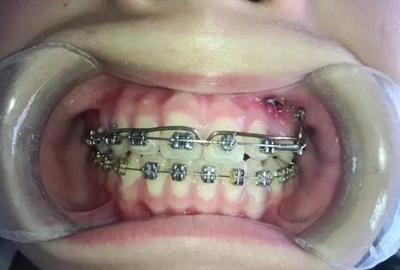

牽引了三四個(gè)月尖牙終于長(zhǎng)出來了,也遠(yuǎn)離了側(cè)切牙

當(dāng)尖牙到達(dá)了指定位置后,又采用了主弓絲和附弓絲,主弓絲采用了不銹鋼絲方絲,有效的避免了反作用力引起相鄰的牙齒出現(xiàn)小開合, 維護(hù)牙弓形態(tài)。

主弓絲和輔弓絲的結(jié)合使用,可以有效避免出現(xiàn)小開合,同志們一定要注意啊!

一個(gè)月后尖牙下來很多,

加上垂直牽引,尖牙下來的更快了